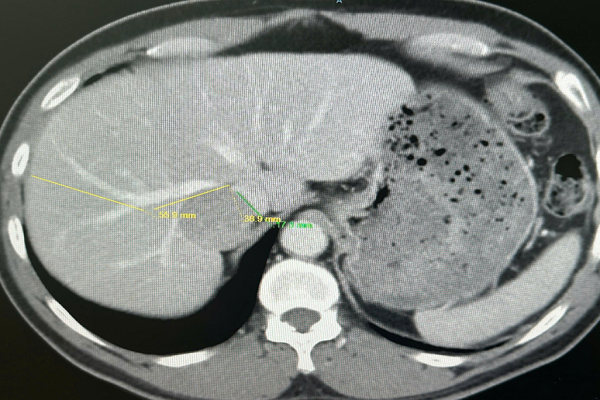

Trước đó, kết quả chụp CT-scan cho thấy, khối u bị vây quanh bởi các mạch máu quan trọng

Khối u 4 cm của bệnh nhân nằm ở vị trí bị bao quanh và chèn ép bởi hệ thống tĩnh mạch gan cùng tĩnh mạch chủ dưới. Trong ngoại khoa gan mật, đây được xem là “vùng cấm” bởi sự nhạy cảm đặc biệt của các cấu trúc giải phẫu.

Chỉ một năm sau, khi quay lại tái khám, kết quả siêu âm và chụp cộng hưởng từ (MRI) đã mang đến một tin như “sét đánh”: chấm trắng nhỏ ngày nào nay đã phát triển thành khối u kích thước khoảng 4 cm. Điều đáng lo ngại không chỉ nằm ở kích thước, mà chính vị trí của khối u mới khiến giới chuyên môn phải dè chừng. Khối u này nằm kẹp giữa các mạch máu trọng yếu, bao gồm tĩnh mạch gan phải và tĩnh mạch chủ dưới.